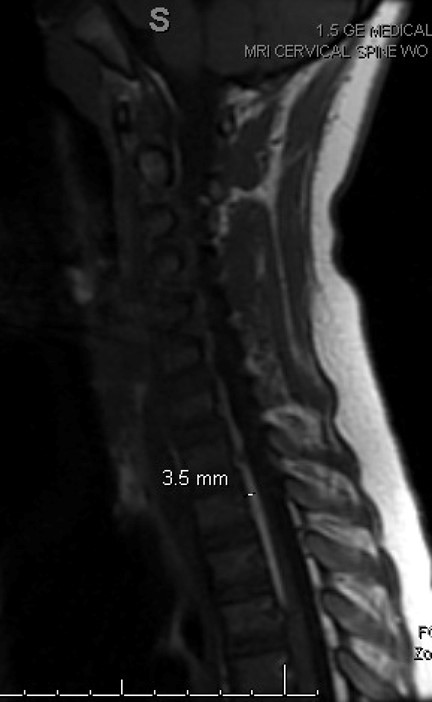

Pediatric surgery was consulted due to the patient’s recent traumatic head injuries. Acute torticollis was suspected, and no imaging was recommended. However, due to the patient’s worsening status, limited range of motion, and impact on daily living, MRI cervical spine was obtained.

Imaging revealed a cervical subdural hematoma that extended into the thoracic region. Subsequent MRI images of the thorax and lumbar spine were obtained. The patient was admitted for observation, pain control, and neurosurgery evaluation. There was no surgical intervention, and the patient was cleared by physical therapy and occupational therapy for home, and the patient will follow up with neurosurgery for repeat MRI images.